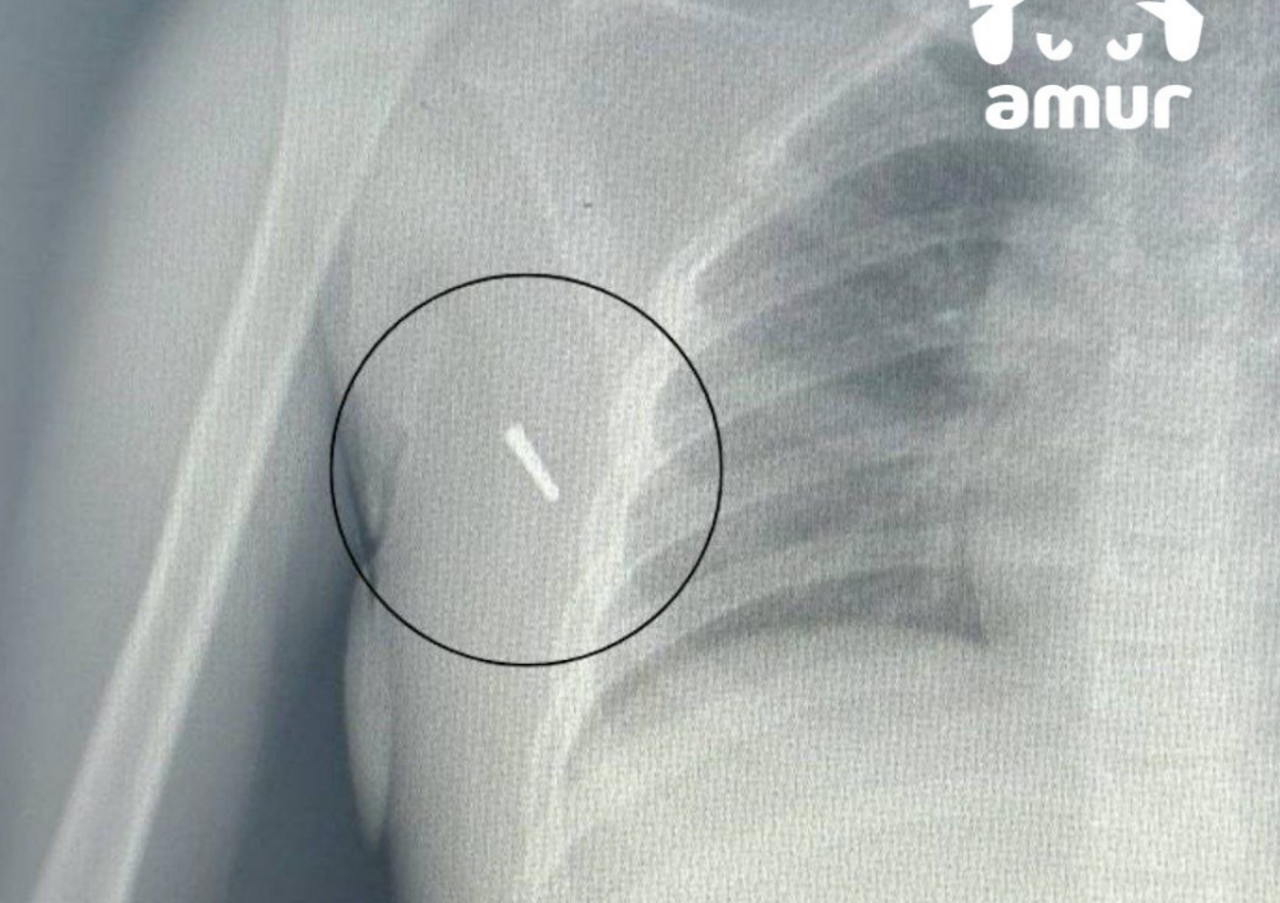

Ртутный градусник вонзился в подмышку восьмилетней девочки в Приморье

В Артеме восьмилетняя девочка ехала на машине и измеряла температуру с помощью ртутного термометра. В какой-то момент автомобиль попал в аварию, из-за чего градусник раскололся. Один из осколков вонзился в подмышку девочки.

Маленькую пострадавшую госпитализировали во Владивосток, где провели операцию. Уже спустя несколько дней ребенка выписали, сообщает Telegram-канал Amur Mash.

Фото: Telegram / Amur Mash